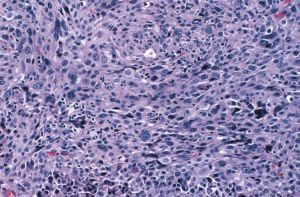

(1)肉眼觀:腫塊較大,病變不規則,無包膜,廣泛浸潤、破壞,切面灰白,常有出血、壞死。(2)鏡下:癌細胞大小、形態、染色深淺不一,核分裂像多。組織學上可分為小細胞型、梭形細胞型、巨細胞型和混合細胞型。可用抗Keratin、CEA及thyroglobulin等抗體作免疫組織化學染色證實是否來自甲狀腺腺上皮。

甲狀腺未分化癌(2)鏡下:癌細胞大小、形態、染色深淺不一,核分裂像多。組織學上可分為小細胞型、梭形細胞型、巨細胞型和混合細胞型。可用抗Keratin、CEA及thyroglobulin等抗體作免疫組織化學染色證實是否來自甲狀腺腺上皮。